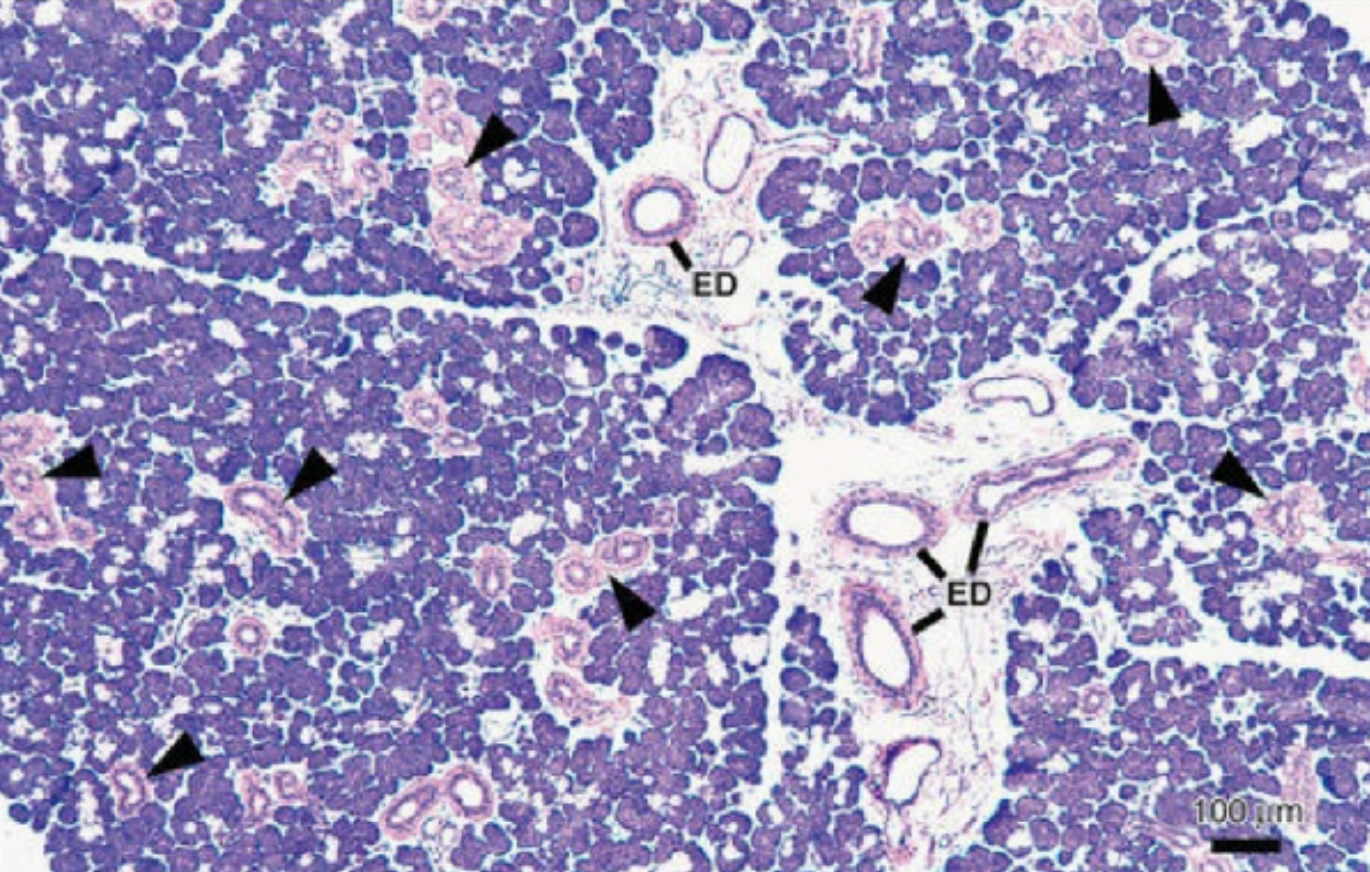

The functional unit of the salivary glands is acini (saliva).

Three types of salivary glands are: Serous, mucous, and seromucous (mixed)

The secretion from the acini (saliva) first reaches the intercalated ducts and then into the striated ducts. these ducts are between the acini and so inside the lobular arrangment.

Finally the contents reach the collecting or exceratoey duct which are present in between the lobules called interlobular ducts

Ducts:

Execratory ducts

striated ducts

intercalated ducts

Ducts of the salivary gland:

Striated ducts:

Columnar cells

Centrally located nucleus

Eosinophilic cytoplasm

Prominenty striations

Intercalated Ducts:

Smaller in diameter

lined by small cuboidal cells

Nucleus located ar the center

Myoepithelial cells are also present

Excretory ducts:

Located in the connective tissue septa between lobules of the gland

Ducts are larger than striated ducts

In large excretory ducts goblet cells may be present between basal cells

As the duct reaches the oral mucosa the lining becomes stratified